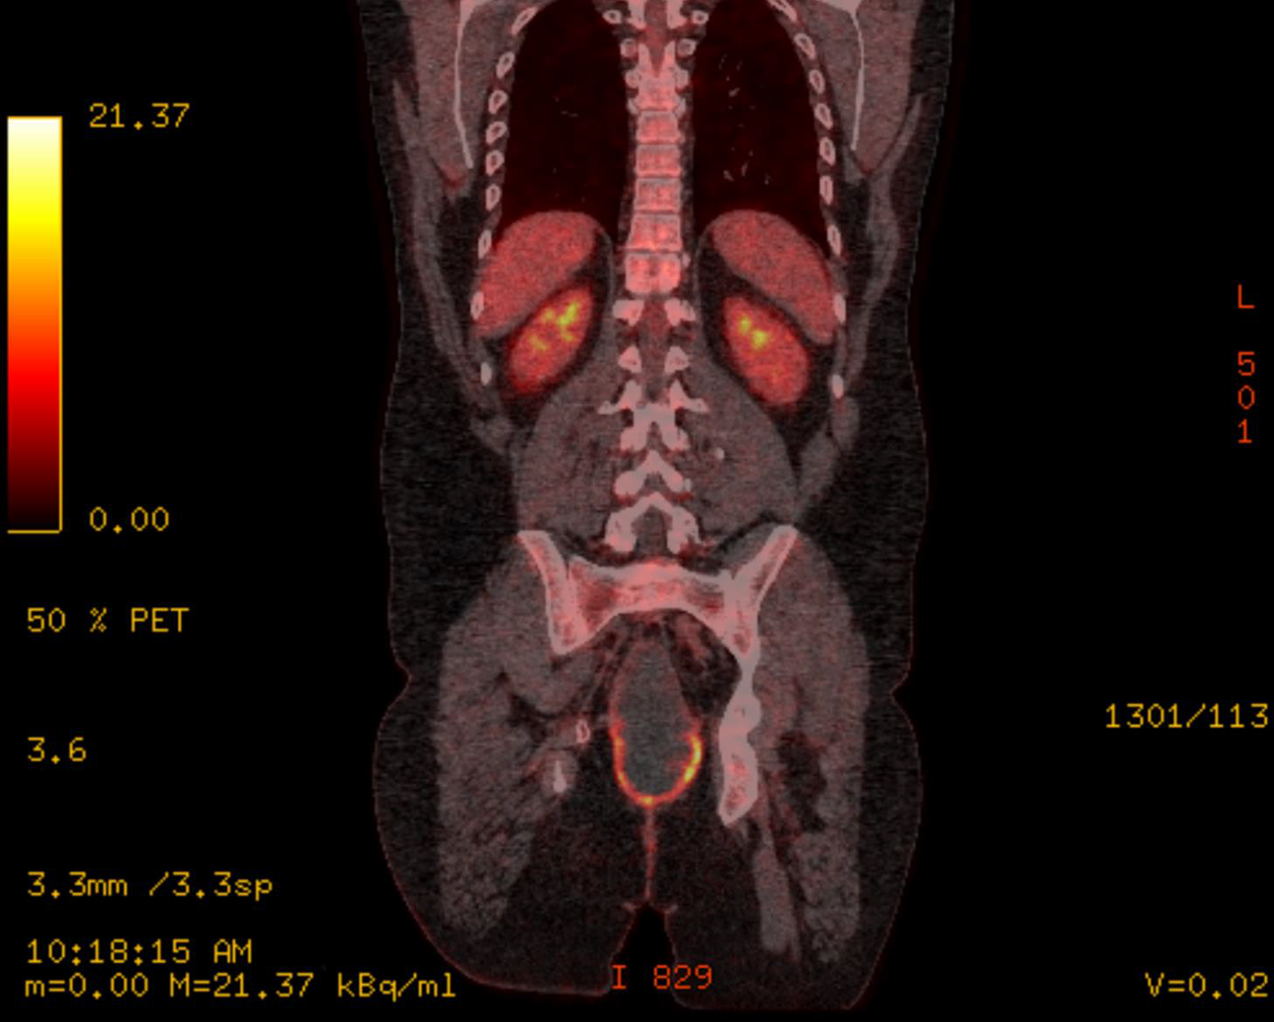

Following surgery, he had adjuvant chemotherapy with capecitabine and oxaliplatin (8 cycles) followed up by the standard colorectal surveillance program. During his second year of follow up, he developed some mucoid discharge from a perineal sinus. Further imaging computer tomography (CT) scan then Positron emission Tomography (PET) Scan (Figure 3) revealed a pelvic cystic lesion, which was inconclusive on the PET scan.